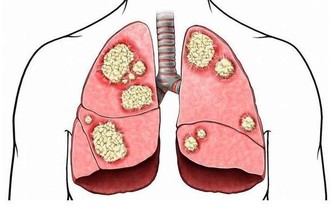

3、骨關節炎---最常見的關節病。

是軟骨磨損導致的關節病,主要表現為關節疼痛,稍活動後減輕,過度活動後又加重。治療是吃非甾體類抗炎藥、鍛鍊和減肥,一般不用手術治療。 但風濕性關節炎患者的關節軟骨破壞較嚴重的,需要做膝關節置換術。